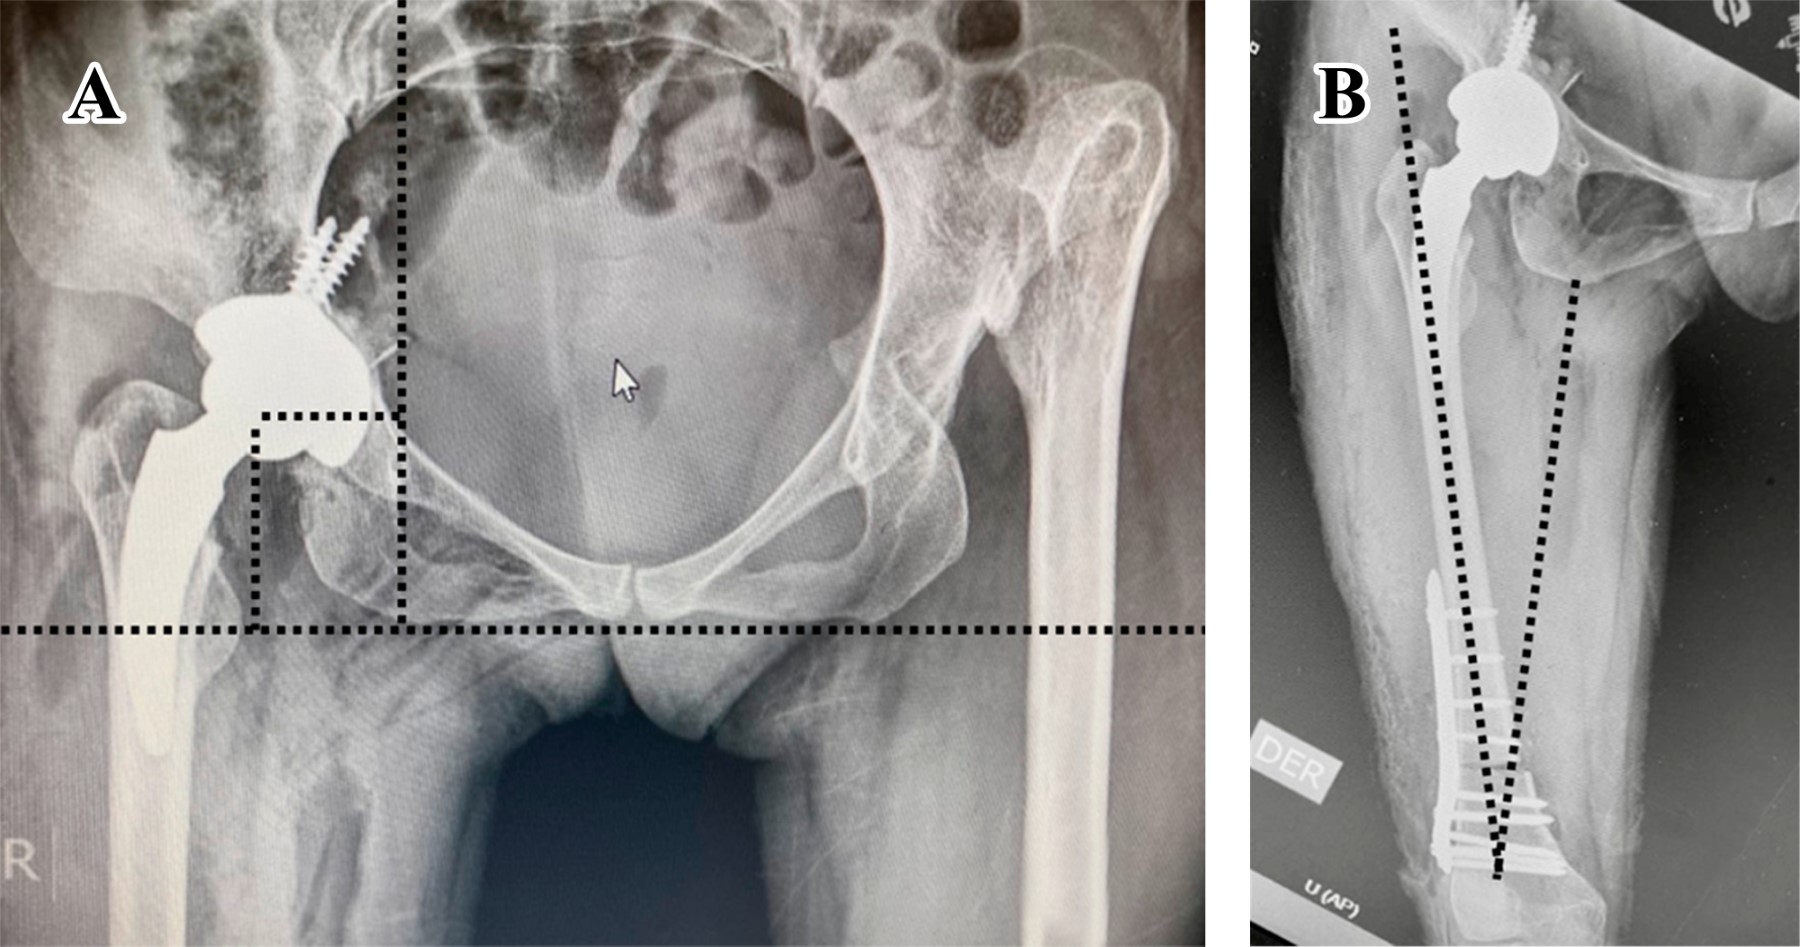

Se realiza irrigación de heridas quirúrgicas, reinserción de colgajo muscular de los glúteos con vicryl 2.0 y fascia lata con el mismo tipo de sutura, cierre de tejido celular subcutáneo y piel con punto subdérmico y misma secuencia de cierre en herida distal. Se mantiene a la paciente en posición de cubito supino, extremidad con 15° de flexión de rodilla e indicaciones de no deambular hasta nueva orden e indicación de radiografía postoperatoria (Figura 13). Durante el tiempo transoperatorio se reportó un sangrado de 300 cm3, sin tener la necesidad de transfusiones, libre de accidentes e incidentes, con cuenta de textiles completa y tiempo quirúrgico de 90 minutos; la paciente sale de la sala en estado estable. Se llevó a cabo una revisión a las tres semanas para retiro de puntos; se continua con indicación de diferir apoyo hasta presentar datos radiográficos sugerentes de consolidación, con citas subsecuentes a las cuatro, ocho, 12 y 16 semanas con controles radiográficos. Se decide apoyo parcial a las seis semanas y total a las 12. Se presentaron parestesias en el dermatomo L5 y S1, conservando integridad motora de los mismos niveles. Se observa radiográficamente consolidación a las 16 semanas por escala de Montoya. Sobre las mediciones radiográficas, observamos una recuperación nativa del CRCF, inclinación del componente acetabular de 43° y anteversión de 13° obtenida por el método de Widmer, ambos ángulos dentro de la zona de seguridad de Lewinnek, efecto Voss neutro y Offset externo de 35 mm; se observa la presencia de tornillos de fijación acetabular endopélvicos, situación esperada por las características displásicas del acetábulo al carecer de una cobertura ósea adecuada y paredes delgadas (Figura 13A); en relación a los ejes mecánicos y anatómicos, se conserva una adecuada angulación en asociación con la rodilla con un ángulo Q 18°, considerado dentro de los parámetros normales (Figura 13B).

Figura 13